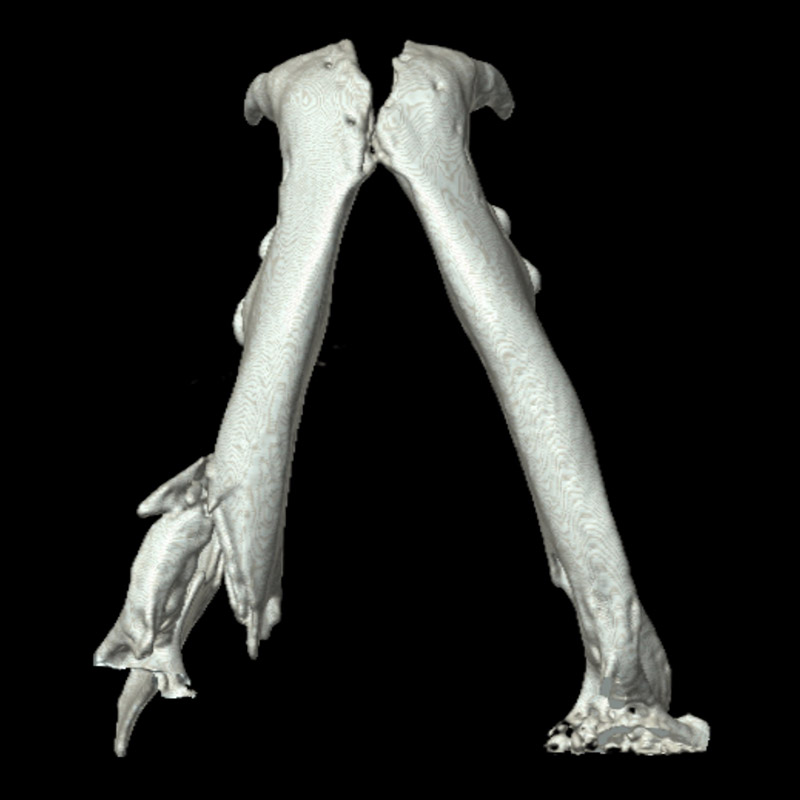

下顎骨骨折

雑種猫(14歳)

犬に咬まれた

手術前

手術後

CT正面